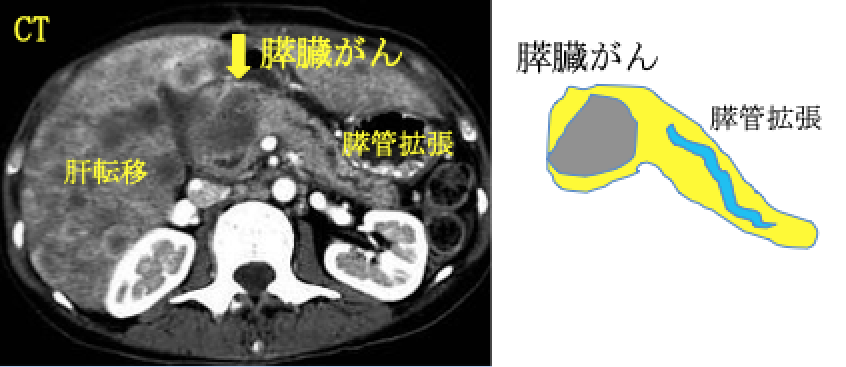

膵臓がんはすい管(消化液〈=すい液〉の通り道)から発生する膵管がんと言われています。 膵臓がんを発症すると、すい管が狭くなり、膵液が停滞します。その際に、主膵管拡張・膵のう胞(分枝膵管拡張)・脂肪変性(膵臓の凹みや痩せ)・腫れといった変化を引き起こします(膵臓がんの間接所見)。これにともなって、膵臓の炎症を起こしたり(みぞおちの痛み)、膵臓のはたらきが低下します(糖尿病の発症や悪化、味覚の変化、下痢など)。顕微鏡レベルの膵臓がん(上皮内がん)でも上記の間接所見や症状を伴うものがあることがわかってきました。膵臓がんが発生してから転移するまで約7年かかると言われております。この間に膵臓の形や膵管の変化をとらえることで早期の膵癌が発見できる可能性があります。

③ CT(シーティー)

膵臓がんがわかりにくいことがあります。造影剤を使用することでがんの存在やひろがりがわかります(腎臓が悪かったり、喘息などがあると造影剤を使用できないことがあります)。“膵癌になりやすい”要素である、膵管拡張・膵のう胞・膵臓の形の変化(脂肪変性:凹みや痩せ、腫れ)がわかります。